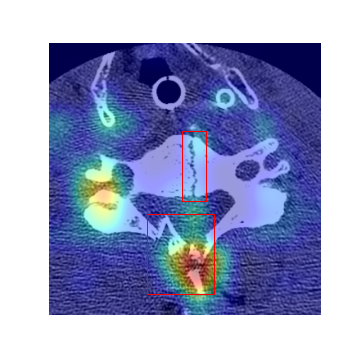

Refer to caption

\alphalph Axial image with three fractures.

\alphalph Heatmap of (a).

\alphalph Axial image with two fractures.

\alphalph Heatmap of (c).

Fig. 3: (a),(c): Samples of cervical spine axial images with fracture; (b),(d): Grad-CAM [10] heatmap from the last layer of ResNet-50 corresponding to (a) and (c), respectively. Ground-truth is represented with red boxes.

Figure 3 shows two samples of axial cervical spine images with corresponding ground-truth masks and heatmaps generated using Grad-CAM [10] from the last layers of ResNet-50. The heatmaps show ResNet-50 can capture most fracture areas with a relatively high false positive rate. Classification performance of the ResNet-50 at image level fracture detection in cervical spine axial images is presented in Table 2. In this experiment, cervical spine fracture is predicted just based on the spatial features in each axial image without counting temporal information. The results show 80.01%percent80.0180.01\% and 77.61%percent77.6177.61\% classification accuracy for the imbalanced and balanced datasets, respectively. However, the main drawback of this approach is the high level of false positives which leads to an inaccurate prediction for the entire case. Such that even if a single image in a case is false positive, the entire case will be false positive and vice-versa. These results show the importance of incorporating temporal features in training and inference. Table 3 shows performance results of the combined BLSTM and ResNet-50 model at the case level for different number of LSTM units. The results regarding the imbalanced dataset show as the number of units increases from 969696 to 256256256, the classification accuracy also increases from 75.79%percent75.7975.79\% to 79.18%percent79.1879.18\%. However, the accuracy is approximately 71%percent7171\% for the balanced dataset and it is less dependent on the number of LSTM units.